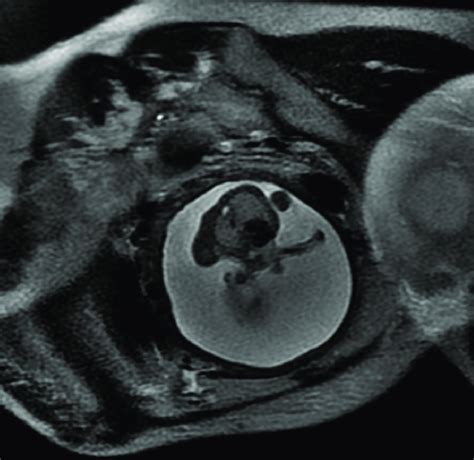

SSFSE/T2/ax. Case 13. Unusual pair of conjoined...